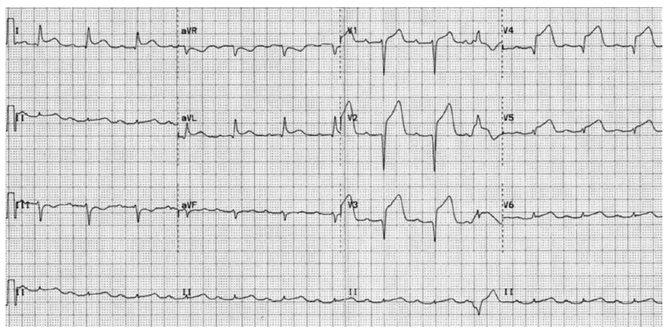

Paciente do sexo masculino, 64 anos, portador de hipertensão arterial, obesidade grau 2, diabetes mellitus tipo 2, com história de dor torácica retroesternal opressiva iniciada há 90 minutos, irradiando para braço esquerdo e mandíbula, associada a náuseas, vômitos e sudorese intensa. Foi levado ao pronto-socorro pelo SAMU. Na chegada, encontra-se ansioso, dispneico e sudorese fria. Ao exame físico: PA: 86 × 58 mmHg FC: 112 bpm. Consciente e orientado, sem déficits motores. Ritmo cardíaco regular 2 tempos sem sopros. Murmúrio vesicular presente com estertores crepitantes bibasais. Extremidades frias, tempo de enchimento capilar de 5 s.

Realizou o eletrocardiograma a seguir:

(Arquivo pessoal; arquivo usado com autorização)

Qual a conduta correta em relação à reperfusão nesse paciente?

Paciente do sexo masculino, 64 anos, portador de hipertensão arterial, obesidade grau 2, diabetes mellitus tipo 2, com história de dor torácica retroesternal opressiva iniciada há 90 minutos, irradiando para braço esquerdo e mandíbula, associada a náuseas, vômitos e sudorese intensa. Foi levado ao pronto-socorro pelo SAMU. Na chegada, encontra-se ansioso, dispneico e sudorese fria. Ao exame físico: PA: 86 × 58 mmHg FC: 112 bpm. Consciente e orientado, sem déficits motores. Ritmo cardíaco regular 2 tempos sem sopros. Murmúrio vesicular presente com estertores crepitantes bibasais. Extremidades frias, tempo de enchimento capilar de 5 s.

Realizou o eletrocardiograma a seguir:

(Arquivo pessoal; arquivo usado com autorização)

Qual a conduta correta em relação à reperfusão nesse paciente?

Leia o caso clínico a seguir para responder à questão:

Paciente do sexo masculino, 64 anos, portador de hipertensão arterial, obesidade grau 2, diabetes mellitus tipo 2, com história de dor torácica retroesternal opressiva iniciada há 90 minutos, irradiando para braço esquerdo e mandíbula, associada a náuseas, vômitos e sudorese intensa. Foi levado ao pronto-socorro pelo SAMU. Na chegada, encontra-se ansioso, dispneico e sudorese fria. Ao exame físico: PA: 86 × 58 mmHg FC: 112 bpm. Consciente e orientado, sem déficits motores. Ritmo cardíaco regular 2 tempos sem sopros. Murmúrio vesicular presente com estertores crepitantes bibasais. Extremidades frias, tempo de enchimento capilar de 5 s.

Realizou o eletrocardiograma a seguir:

(Arquivo pessoal; arquivo usado com autorização)

Qual a conduta correta em relação à antiagregação plaquetária nesse paciente?

Paciente do sexo masculino, 64 anos, portador de hipertensão arterial, obesidade grau 2, diabetes mellitus tipo 2, com história de dor torácica retroesternal opressiva iniciada há 90 minutos, irradiando para braço esquerdo e mandíbula, associada a náuseas, vômitos e sudorese intensa. Foi levado ao pronto-socorro pelo SAMU. Na chegada, encontra-se ansioso, dispneico e sudorese fria. Ao exame físico: PA: 86 × 58 mmHg FC: 112 bpm. Consciente e orientado, sem déficits motores. Ritmo cardíaco regular 2 tempos sem sopros. Murmúrio vesicular presente com estertores crepitantes bibasais. Extremidades frias, tempo de enchimento capilar de 5 s.

Realizou o eletrocardiograma a seguir:

(Arquivo pessoal; arquivo usado com autorização)

Qual a conduta correta em relação à antiagregação plaquetária nesse paciente?